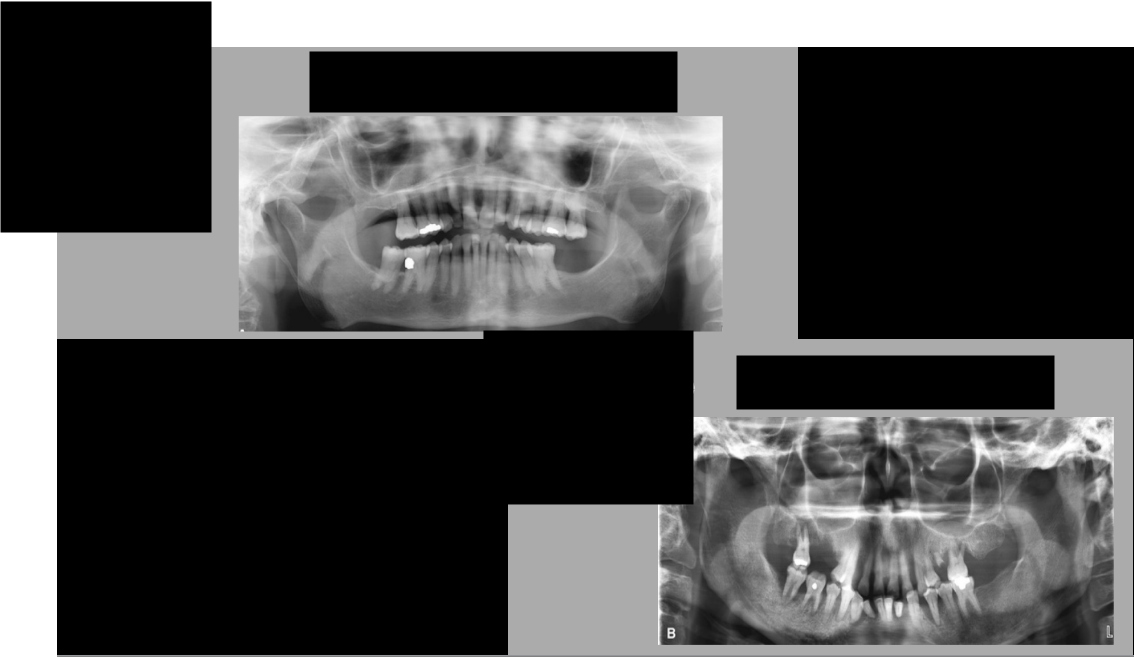

What error (s) do we see here?

A. Head rotated or twisted to right more

B. Head rotated or twisted to the left more

C. Chin too high

D. Chin too low